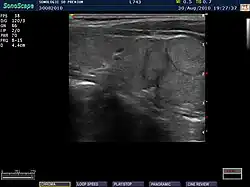

Ultrasound

An ultrasound may be useful in detecting Hashimoto thyroiditis, especially in those with seronegative thyroiditis,[13] or when patients have normal laboratory values but symptoms of autoimmune thyroiditis.[47] Key features detected in the ultrasound of a person with Hashimoto's thyroiditis include "echogenicity, heterogeneity, hypervascularity, and presence of small cysts."[13] Images obtained with ultrasound can evaluate the size of the thyroid, reveal the presence of nodules, or provide clues to the diagnosis of other thyroid conditions.[47]